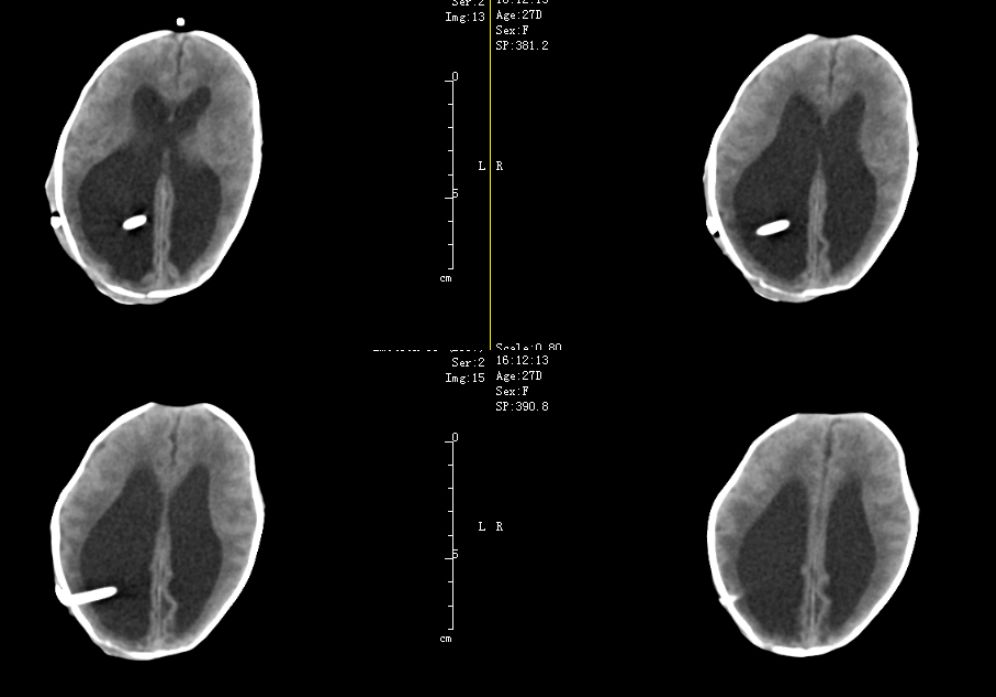

病例1,治疗观察2周后头围较前明显增大,由32.5cm增大至35.0cm,体重由1560g增长至1840g,查B超提示左侧脑室体宽4.42cm,右侧脑室体宽4.95cm,第三脑室扩张约1.1cm。侧脑室形态不规则,B超测量取决层面差异,三脑室有增大情况,考虑脑积水,遂决定行脑室腹腔分流术。

病例2治疗观察2周后复查头围较前变化不大,由31.0cm增加至32.5cm,体重由1410g增加至1910g,查B超提示:左侧侧脑室体宽2.9cm,右侧体宽2.4cm,第三脑室宽1.0cm,有进行性增大趋势,也决定行VP分流术。

2例患儿均行枕角穿刺(图2),植入美敦力公司的可调压分流管,术后压力调节在1.5档。2例患儿术后恢复良好,无感染、分流管堵塞等并发症,顺利出院。并一直随访复查中。

病例1:术后1天CT,见囟门已凹陷。

病例2:术后1天复查CT:前囟门较前平坦。